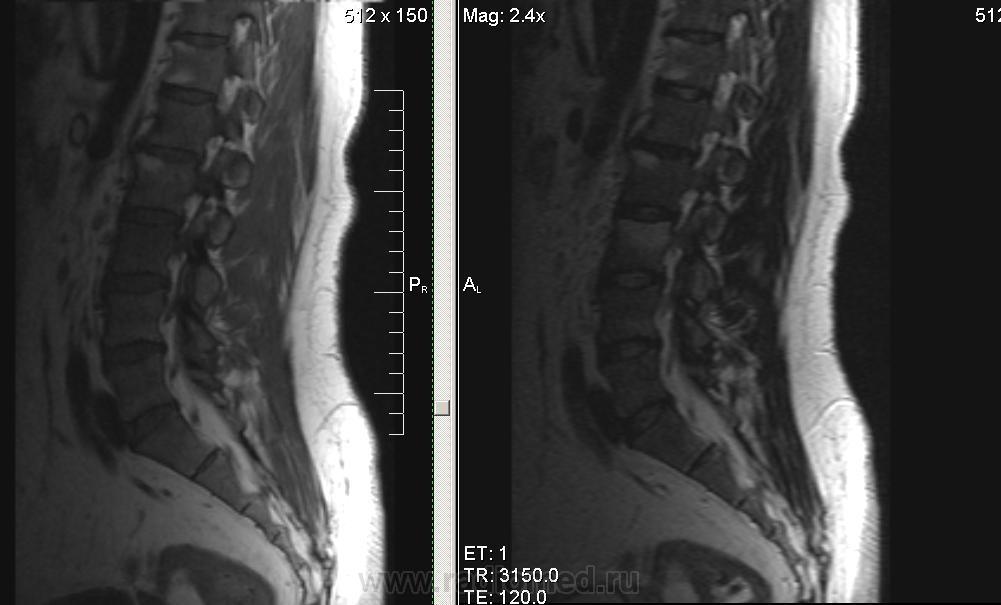

Мужчина, 1974г.р. В течении полугода боли в правой ноге, пояснице. Коллеги, подскажите, пожалуйста, что за системная болячка такая. В грудном отделе - то же самое.

серонегативная спондилоартропатия (?)

Ага, по ссылке Бехтерева.. Тока обычно изменения в области дугоотростчатых суставов и рёберно-позвонковых. У меня было первой мыслью, но суставов на представленных снимках нет.

Сакроилеит. Так что спондилоартрит наиболее вероятен. И боль в правой ноге понятна. Я если у молодых людей причины для корешковых болей не вижу, делаю программу на крестцово-подвздошные суставы. Единственно, в позвоночнике обычно бывает отёк костного мозга апофизов, дугоотростчатых и рёберно-позвонковых суставов.